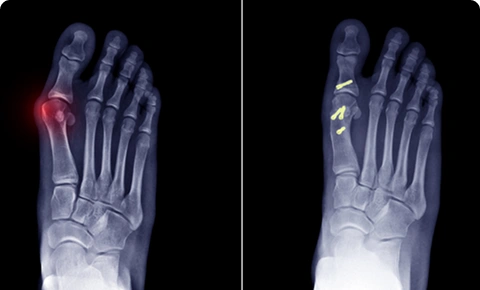

X-ray image of a foot showing bunion deformity before and after correction.

Deformity correction

No two patients are the same. Which is why it takes time to understand your unique bone or joint deformity. Through careful assessment and precise surgical correction, Dr. Easwar helps you regain natural alignment, improved function, and the confidence to move freely again.